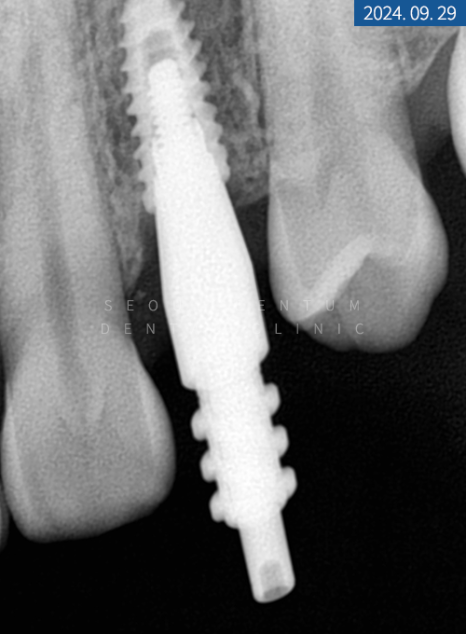

당일 #14번은 잇몸을 열고 GBR 합성골을 이식한 다음 바로 네이바이오텍 픽스처로 고정해 드렸습니다. 환자분이 1차 수술에 진행하길 원하셔서 힐링 어버트먼트로 체결해 드렸죠. 그리고 #24 좌측 소구치는 비절개를 통해 픽스처를 고정한 후 동일하게 힐링 어버트먼트로 체결해 드렸습니다. #14번 소구치는 5개월이라는 골 유착 시간을 가졌으며 #24번은 3개월이 소요되었습니다.

ISQ 장비로 인공 나사와 잇몸뼈가 잘 붙었는지 수치를 체크한 다음 정상 기준에 들어와서 힐링 어버트먼트를 제거하고 코핑을 연결했습니다. 그런 뒤 맞춤 지대주와 크라운 제작을 위해 인상 체득을 하고 다시 힐링 어버트먼트로 연결하게 되었습니다.

2주 후 기공소에서 제작된 커스텀 지대주와 크라운을 수복해 드리면서 마무리했는데요. 치근단 사진을 찍어보니 픽스처 주위에 염증 없이 단단하고 견고하게 고정되었습니다.

두 달 후 재방문을 통해 치근단 사진과 세팔로 사진을 찍어 보니 원하는 위치에 픽스처가 잘 고정돼 있고 주변 구조에 염증 없이 견고하게 자리 잡고 있었습니다. 물론 전체 기간에 환자분이 저작도 마음껏 못하시고 위생 관리에 주의해야 한다는 부분이 있었지만 그래도 수고로운 과정을 견디고 튼튼한 제2의 영구치가 만들어졌습니다.